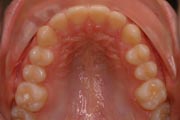

Crowding

After